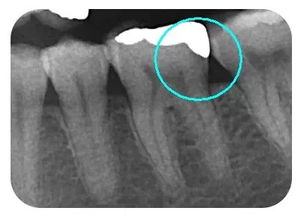

嵌體位于牙體內(nèi)部,只能修復(fù)缺損的牙體組織,不能保護(hù)剩余的牙體組織。

嵌體在咬合受力后會(huì)將力傳導(dǎo)至洞的側(cè)壁,在剩余牙體內(nèi)產(chǎn)生拉應(yīng)力,過大的拉引力會(huì)造成牙體折裂。 要避免咬硬物,注意勿進(jìn)食過硬食物,以免因給牙齒帶來過大的負(fù)荷而影響嵌體的長(zhǎng)期使用。

嵌體位于牙體內(nèi)部,只能修復(fù)缺損的牙體組織,不能保護(hù)剩余的牙體組織。嵌體在咬合受力后會(huì)將力傳導(dǎo)至洞的側(cè)壁,在剩余牙體內(nèi)產(chǎn)生拉應(yīng)力,過大的拉引力會(huì)造成牙體折裂。